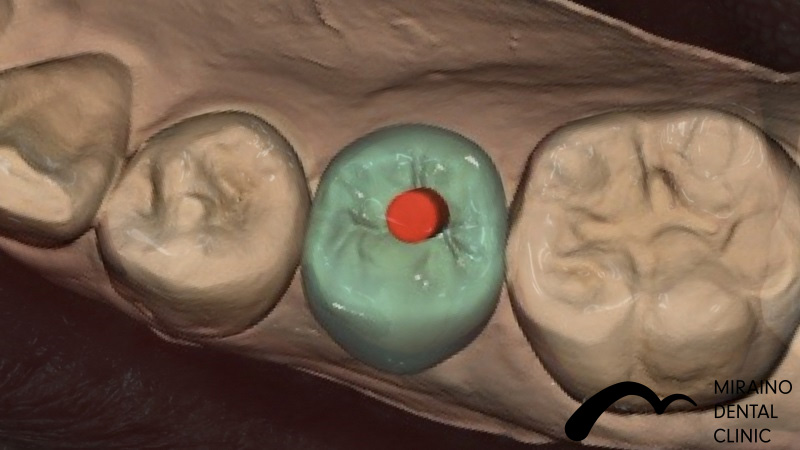

インプラントの症例

Case1

| 施術名 | インプラント |

| 施術の概要 | 10年前ほどに根の先に膿ができて抜歯。 前医では骨が少なくなってしまってインプラントは不可能ということで当院来院。 インプラントOPE時に仮歯まで作成し見た目の回復まで行いました。 その後OPE後3ヶ月で最終の被せ物装着する。 |

クリックして詳細を表示

| 施術の内容 | インプラントは、従来の入れ歯やブリッジとは違い、天然の歯と同じような強くて、美しい歯を取り戻す治療法です。 失った歯の代わりに人工の歯根を埋め込み、その上に人工の歯を装着。 健康な歯を削ることなく、新しい歯が蘇ります。 2~3か月後に上部構造(歯の部分)を装着してかみ合わせを回復させます。 |

|---|---|

| 1歯あたりの治療費 | 450,000円(10年保証込) 骨が薄く造成が必要な場合は追加費用がかかります。 骨造成:30,000円~100,000円 |